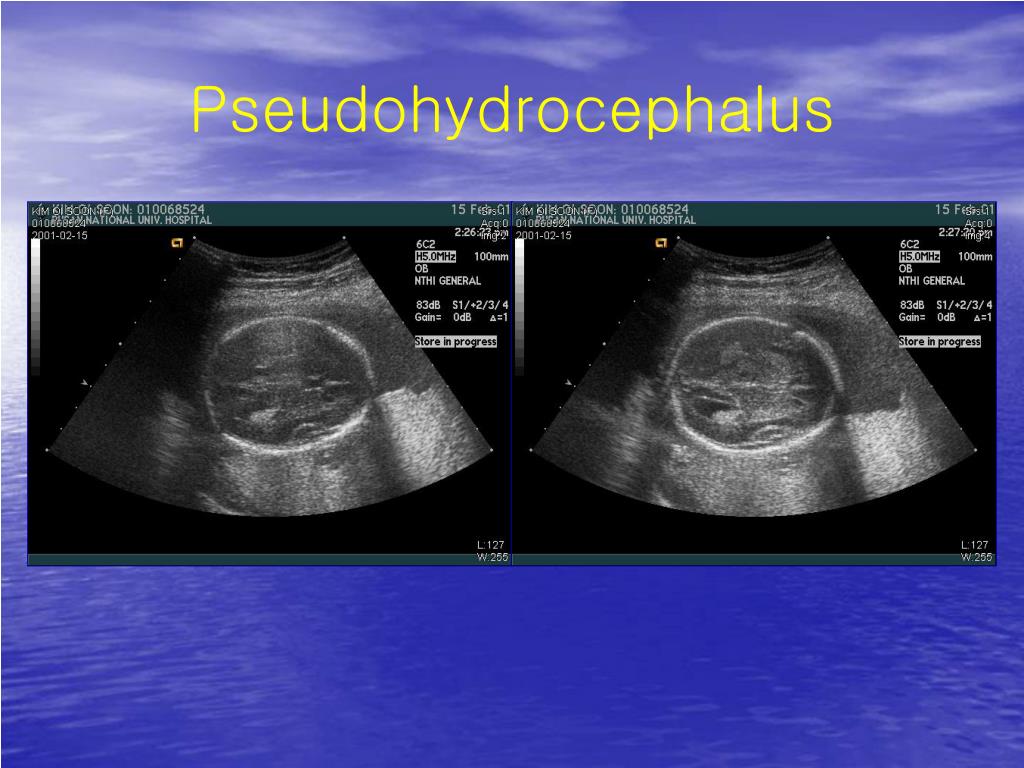

7. Pseudohydrocephalus

5. Fetal CNS • BPD : gestational age • CNS anomalies : TMC birth defects • 3 transverse view • Transthalamic view • Tranventricular view • Transcerebellar view • Errors in interpreting mormal anatomy : ventriculomegaly